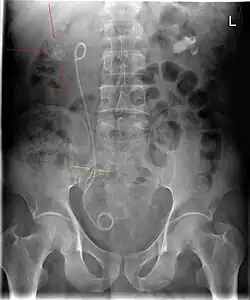

A ureteral stent (pronounced you-REE-ter-ul), or ureteric stent, is a thin tube inserted into the ureter to prevent or treat obstruction of the urine flow from the kidney. The length of the stents used in adult patients varies between 24 and 30 cm. Additionally, stents come in differing diameters or gauges, to fit different size ureters. The stent is usually inserted with the aid of a cystoscope. One or both ends of the stent may be coiled to prevent it from moving out of place; this is called a JJ stent, double J stent or pig-tail stent.

The main complications with ureteral stents are dislocation, infection and blockage by encrustation. Recently stents with coatings, such as heparin, were approved to reduce infection and encrustation to reduce the number of stent exchanges.[2]